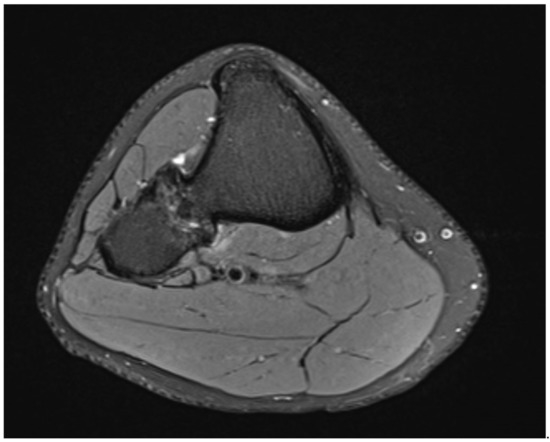

The MRI scan without contrast showed no thickened cartilaginous cap (Figure 3).

The lesions were suspicious for bilateral osteochondroma of the proximal tibiofibular joint and showed no signs of malignancy.

Figure 3. MRI scan in horizontal view showing the synostosis of the right side.